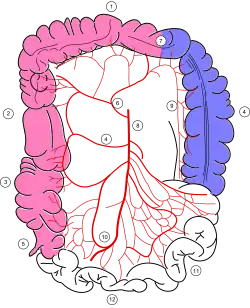

Blutversorgung und Lymphabfluss

Die Abschnitte des Dickdarmes werden von den Ästen dreier großer Arterien versorgt. Blinddarm, Wurmfortsatz, aufsteigendes Colon und der größte Teil des Quercolon erhalten Äste der Arteria mesenterica superior, der restliche Teil des Quercolon, das absteigende Colon, das Colon sigmoideum und das obere Rektum solche von der Arteria mesenterica inferior.[17] Das untere Rektum und der Analkanal erhalten Blut aus der Arteria pudenda interna.[18] Der Blutabfluss erfolgt über Venen, die mit den Arterien verlaufen und gleichlautend benannt sind, also über die Vena mesenterica superior, Vena mesenterica inferior und Vena pudenda interna. Die beiden Erstgenannten münden in die Pfortader der Leber, nur die Vena pudenda interna mündet in die Vena iliaca interna, deren Blut in die untere Hohlvene gelangt, ohne die Leber zu passieren.

Da Lymphgefäße in der Regel mit Arterien verlaufen, entsprechen die Lymphabflussgebiete des Dickdarms in etwa den arteriellen Versorgungsgebieten. Die Lymphe aus dem Stromgebiet der Arteria mesenterica superior fließt über die Mesenteriallymphknoten an der Austrittsstelle der Arterie aus der Bauchaorta (Noduli mesenterici superiores) in den Truncus intestinalis, der in die Cisterna chyli mündet. Die Lymphe aus dem Stromgebiet der Arteria mesenterica inferior gelangt entsprechend über die Lymphknoten neben dem Arterienaustritt (Noduli mesenterici inferiores) und über den linken Truncus lumbalis in die Cisterna chyli.[19]